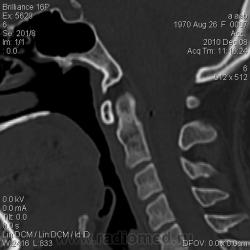

Задняя дуга атланта не замкнута ? И дополнительные бугорки на нижней поверхности тела затылочной.

Гиперпневматизация основной пазухи, и так называемый затылочный позвонок ?

Последняя аномалия, я так понимаю, сращение реберно-поперечного отростка атланта с затылочной чешуей?)

И подвывих атланта. А про сращение... может, Вы и правы. Можно на ассимиляцию думать.